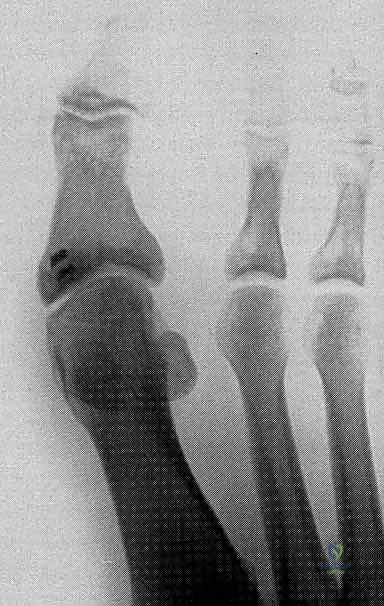

2. مركب العظمين السمسمانيين (Sesamoid Complex)

العظمان السمسمانيان (الإنسي والوحشي) هما عظمان صغيران يشبهان حبة السمسم، ويعملان بنفس الآلية التي تعمل بها صابونة الركبة (الرضفة)، ولكن على نطاق أصغر. يقعان داخل أوتار العضلة المثنية القصيرة لإبهام القدم (FHB) أسفل رأس عظم المشط الأول.

يتم الحفاظ على المسافة بين هذين العظمين بواسطة "الرباط بين السمسمانيين" (Intersesamoid Ligament). في حالات إصابة إصبع القدم العشبي الشديدة، قد يتمزق هذا الرباط أو تنكسر هذه العظام الصغيرة.

* استبعاد وجود كسور في عظام المشط أو السلاميات.

* تقييم العظام السمسمانية (البحث عن كسور أو هجرة غير طبيعية للعظام السمسمانية، مما يدل على تمزق الصفيحة).